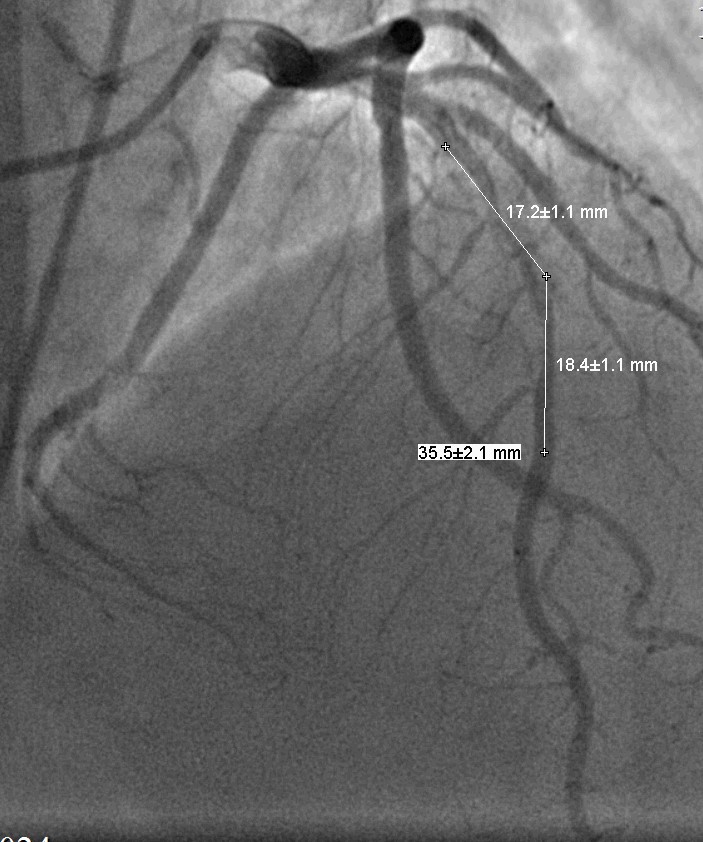

Произведена баллонная ангиопластика со стентированием целевой зоны коронарным стентом (BMS) 3.0х37,0мм.

Контрольная КАГ: просвет ПМЖА в зоне вмешательства полностью восстановлен, остаточный жесткий кальцинированный стеноз среднего отдела стентированного сегмента 50%, антеградный кровоток TIMI III на протяжении по всем артериям.

Выполнена баллонная постдилатация стентированного сегмента баллонным катетером 3,5-24мм.

Контрольная КАГ: среднем отделе выраженная экстравазация контраста, (III тип по Ellis – в анатомическую полость).

Произведено временное перекрытие («пломбирование») просвета ПМЖВ « выше зоны стентирования» баллонным катетером 3,5х24,0мм при Р до 6 атм. (10мин). Подготовка к экстренному стентированию «стент-графтом».

Выполнена имплантация стента-графта Aneugraft 3,5-27,0мм в стентированный сегмент (зону перфорации). Постдилатация.